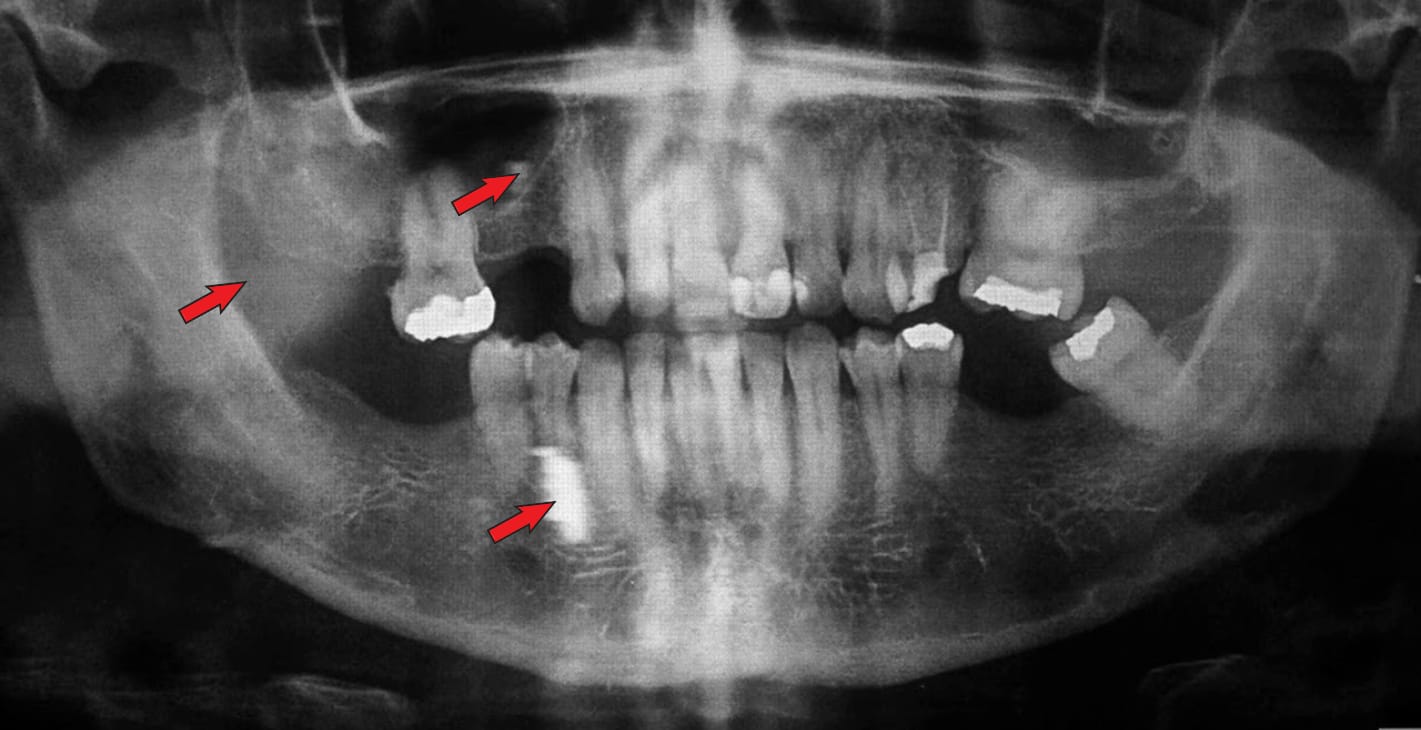

⚠️ Imagem fantasma

Uma imagem fantasma consiste num artefacto radiopaco que é exposto numa imagem panorâmica e é causada pela dupla penetração do feixe de raios X num objecto. Esta imagen fantasma se parece a la imagen real, pero aparece en el lado opuesto de la película, es más grande y más alta que la imagen real y además es difusa.

Solução: Pedir ao paciente que remova todos os objectos metálicos ou radiodensivos, tais como óculos, brincos, piercings, colares, próteses removíveis, aparelhos ortodônticos removíveis, etc.

Imagem 1: imagens fantasma